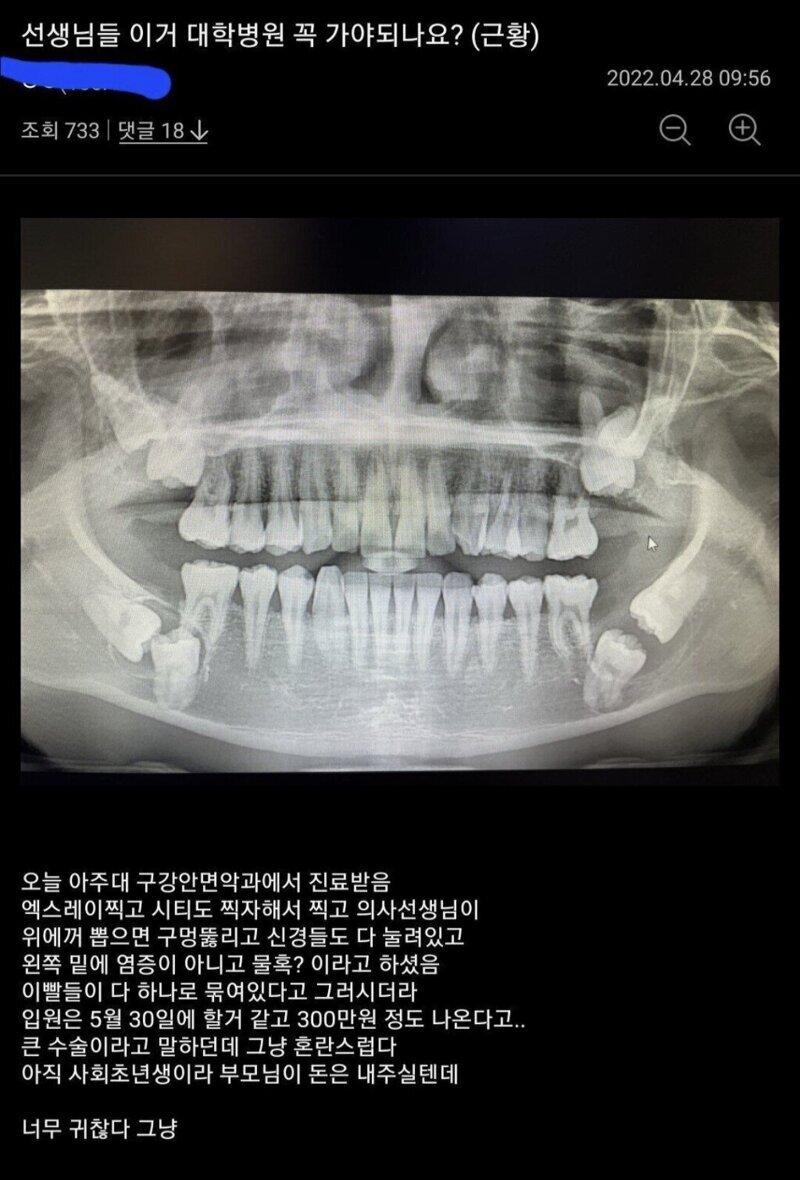

• 작성자최대수혜자 | 작성시간 23.10.14 저거는 함치성낭이나., 뭔가 다른 질병이 포함된 매복치임

• 작성자닐리리야니나니뇨 | 작성시간 23.10.14 이건거의 재앙급인데........